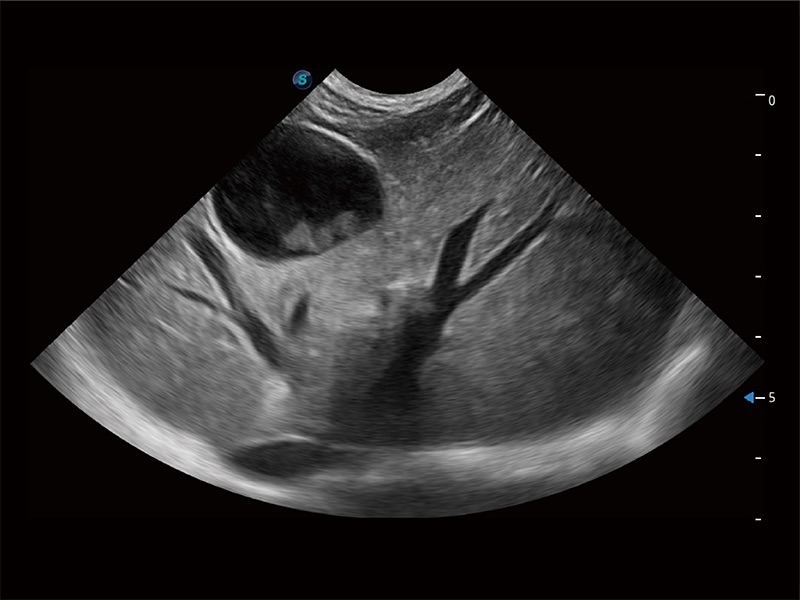

高性能和先進(jìn)的臨床應(yīng)用工具可以為動(dòng)物醫(yī)生提供臨床信心。ProPet 80 搭載了先進(jìn)的腹部和淺表應(yīng)用工具,幫助醫(yī)生在日常臨床實(shí)踐中發(fā)揮前所未有的作用。

極大提升超低速微細(xì)血流的檢出能力,同時(shí)更精準(zhǔn)地濾除軟組織和超聲信號(hào),為獸用醫(yī)生提供以往無(wú)法通過(guò)常規(guī)血流獲得的疾病診斷信息。

在傳統(tǒng)二維血流成像的基礎(chǔ)上,呈現(xiàn)血流的立體感,具有動(dòng)感的生命力之美。即便是微小的血管也能輕松應(yīng)對(duì),提高了血流的視覺(jué)敏感性。